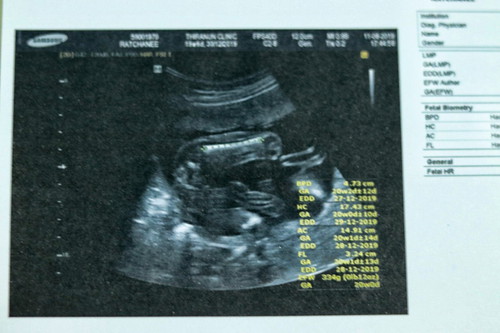

แม่ๆช่วยหนูดูหน่อยคะ?

เเบบนี้ผู้ หญิง หรือ ผู้ ชายคะ หมอบอก เป็นผู๊หญิง อยากเหนภาพซาวของเเม่ๆบ้างคะ ❤❤❤

ถ้าจากในรูปนี้ น่าจะหญิงค่ะ ไม่มีกระปู๋ แต่รอดูอีกหน่อยก็ได้จ้า

ไม่มีติ่งยื่นออกมา น่าจะผู้หญิงนะคะ

หญิงค่ะ ไม่มีอะไรยื่นออกมา